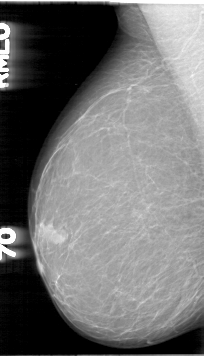

D_4003_1.LEFT_MLO

RIGHT_MLO LINES 5326 PIXELS_PER_LINE 3046 BITS_PER_PIXEL 12 RESOLUTION 43.5 NON_OVERLAY